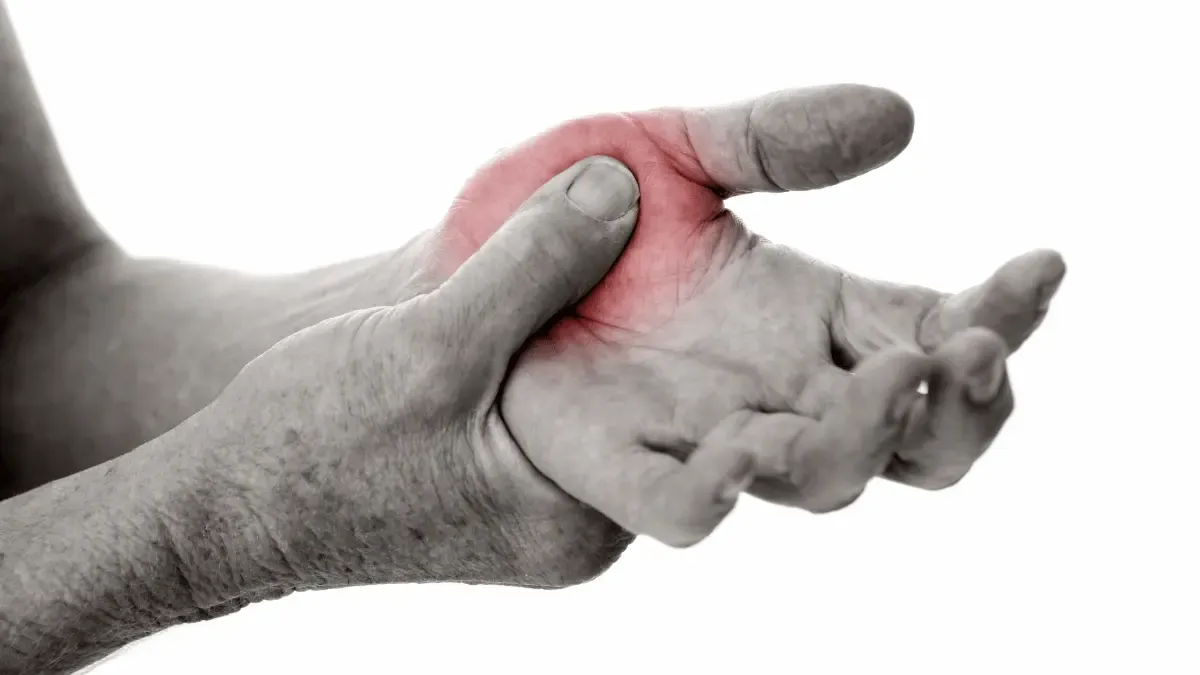

Ao longo da minha trajetória como ortopedista especializado em cirurgia da mão e punho, a bossa carpal é uma das condições mais frequentes que encontro em meu consultório. Esta protuberância no dorso do punho, tecnicamente conhecida como cisto...